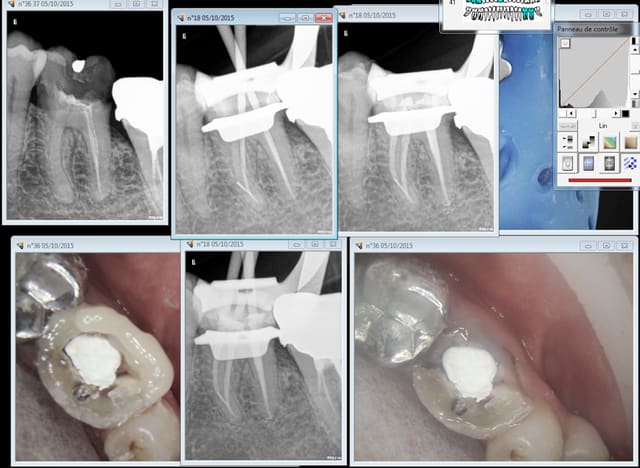

En ce moment j'ai pas vraiment le feu sacré en endo. que pensez vous de cette 36? Est ce que je retourne dans les canaux distaux pour gagner le dernier millimètre? vu que c'est un pote j'ai pas trop le choix...

Radios cones en place, ciment en place et finale après thermo compaction, toujours.

tu as instrumenté jusqu'au bout et c'est juste l'obtu qui a foiré ou est ce que tu n'as jamais atteint le bout?

Si t'as instrumenté jusqu'au bout bien irrigué et que ce sont justes tes cônes de gutta qui te l'ont fait à l'envers (ça m'arrive aussi des fois, radio maitre cône impec, radio final il manque 1mm...) ben le pronostique reste bon et retrouver ta longueur sera facile si tu veux retraiter.